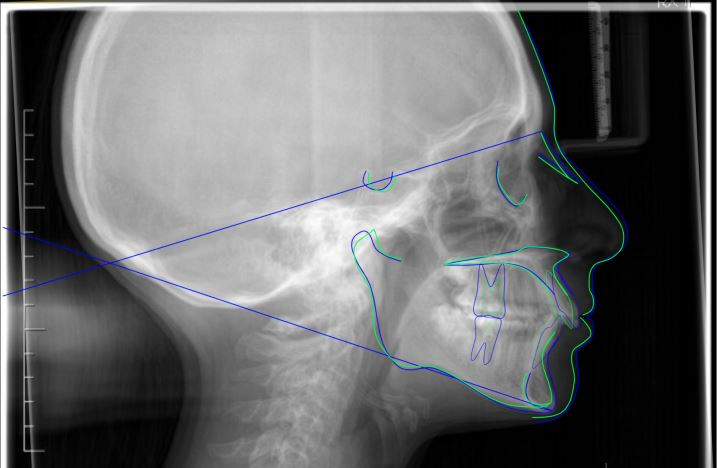

Teleradiografia latero-laterale pre-trattamento

Fig. 2 Teleradiografia latero-laterale pre-trattamento

Sovrapposizione dei tracciati cefalometrici

Fig. 9 Sovrapposizione dei tracciati cefalometrici pre (blu) e post (verde) trattamento (piano di riferimento SN) con l'apposita funzione della piattaforma Cephio